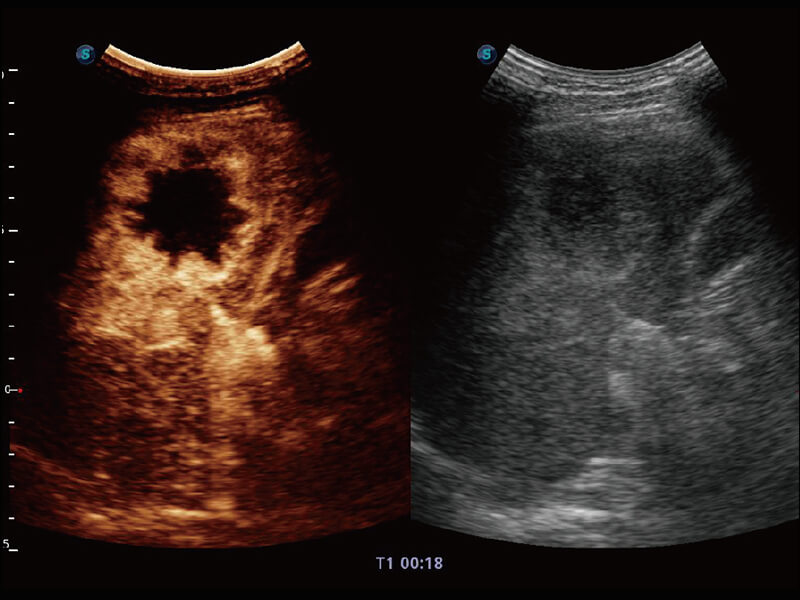

性能优异的硬件架构,极大提升超声系统的运行效率和数据处理能力。相比以往超声成像系统,Wis+平台为您带来极快的响应速度和成像帧频,提升检查流畅度。

超宽频带技术,为容积成像带来优质的二维图像基础,为您呈现丰富的结构细节,栩栩如生地展示宝宝的宫内形态以及各种组织的立体结构。